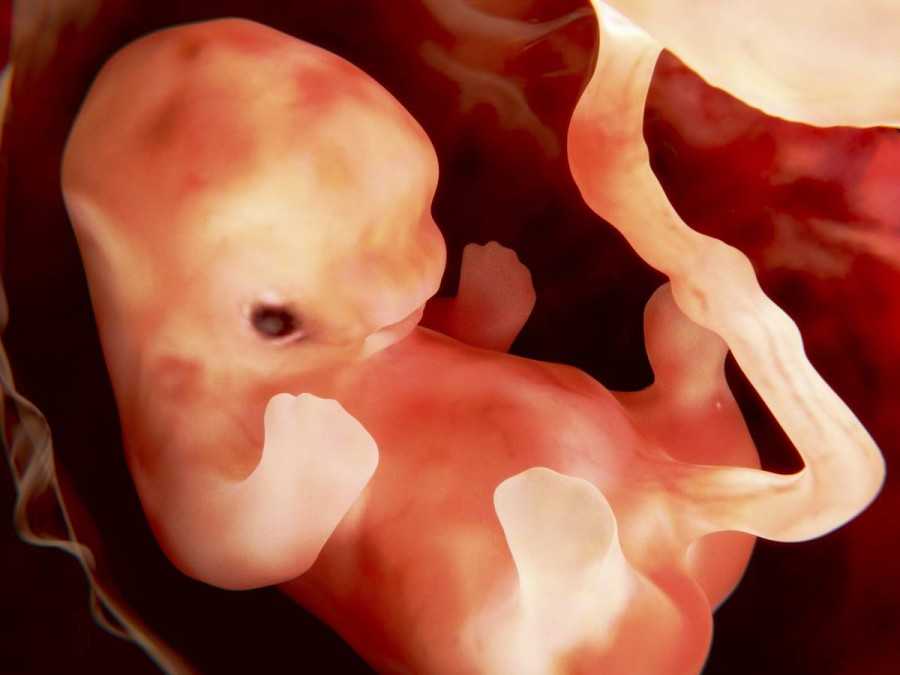

Вот так выглядит твой малыш на 9 неделе (фото плода)

Фото плода и живота матери на сроке 9 недель

Как выглядит эмбрион на 9 неделе? Ваш кроха еще подрос. У него уже начинает формироваться личико, удлиняются конечности, появляются пальчики. Именно на данном этапе ребенок прогрессирует и становится не эмбрионом, а плодом, поскольку большой палец на руке разворачивается так, что прижимается к ладони с внутренней стороны (противостоящий палец).

Уже можно заметить пуповину. И именно с этой недели ваш малыш начинает развиваться быстрее вдвое.